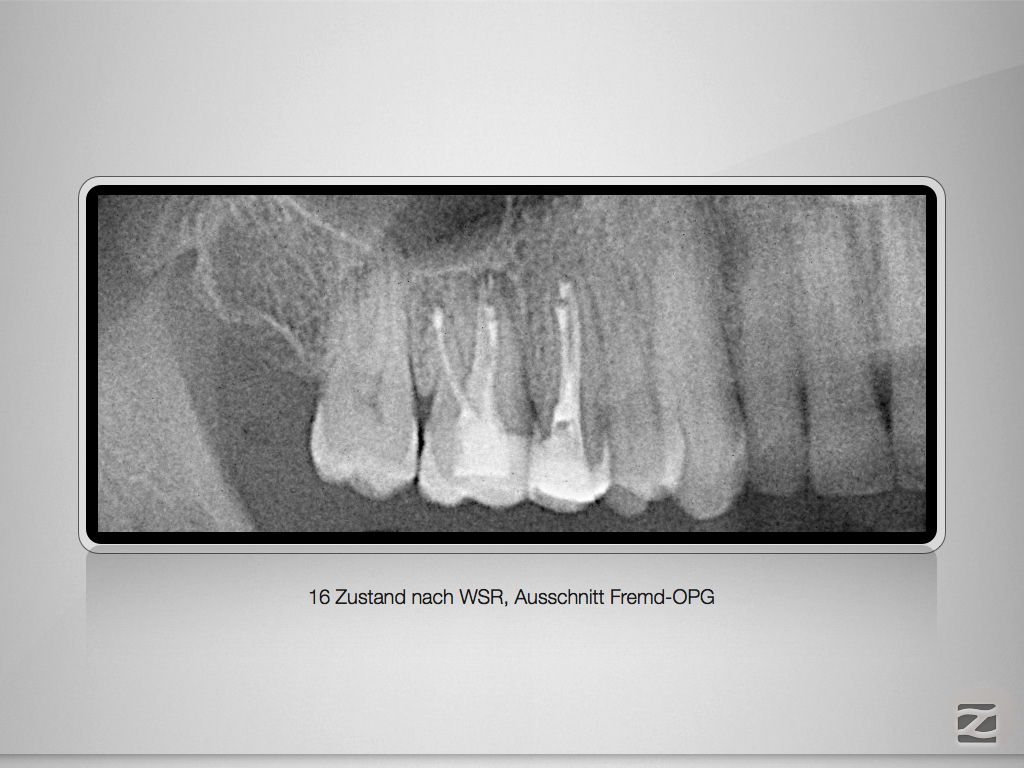

16d-001

Revision nach Resektion